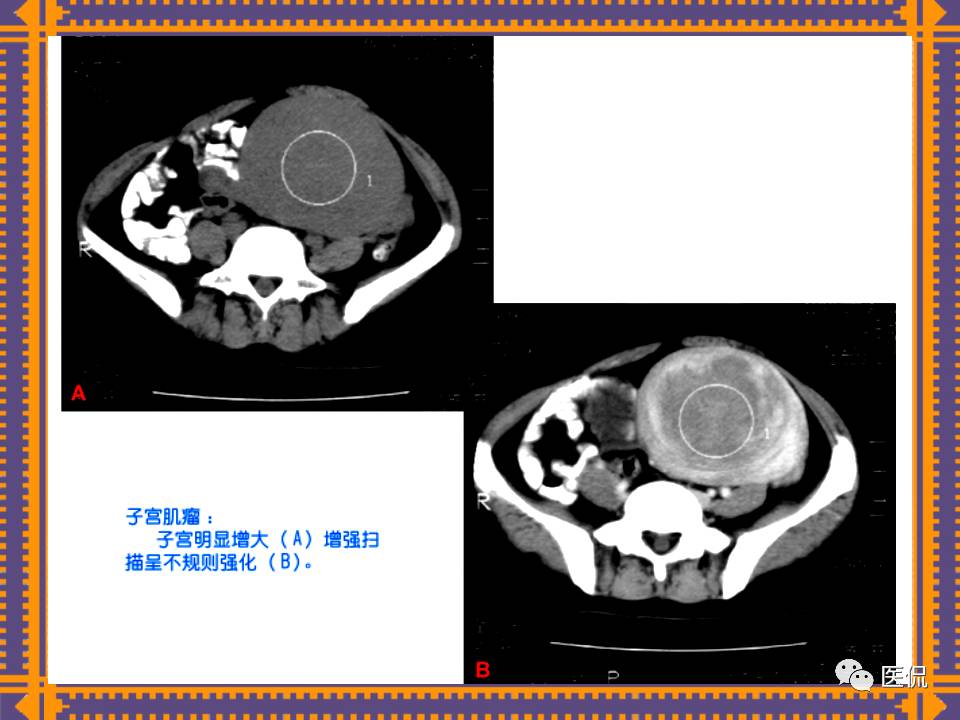

这篇PPT对男性生殖系统疾病:前列腺增生、前列腺癌;女性生殖系统疾病:子宫肌瘤、子宫癌、卵巢囊肿和卵巢肿瘤以及腹膜后间隙疾病进行了详细讲解。